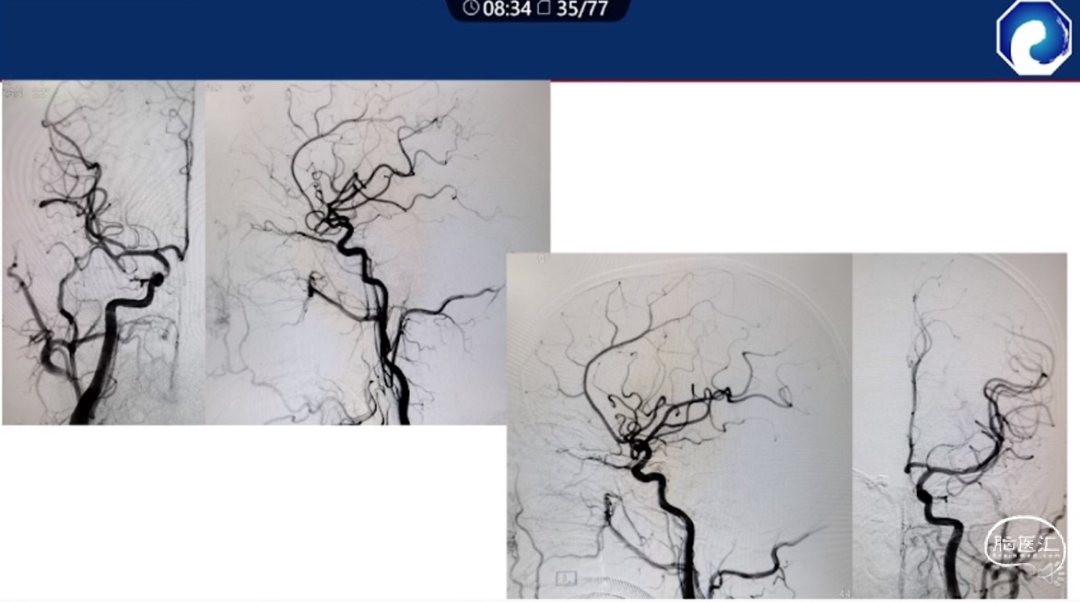

痿口静脉端精准完全闭塞是DAVF治愈的关键。

减少栓塞材料应用。

减少与颈内动脉重叠,避免栓塞材料意外栓塞。